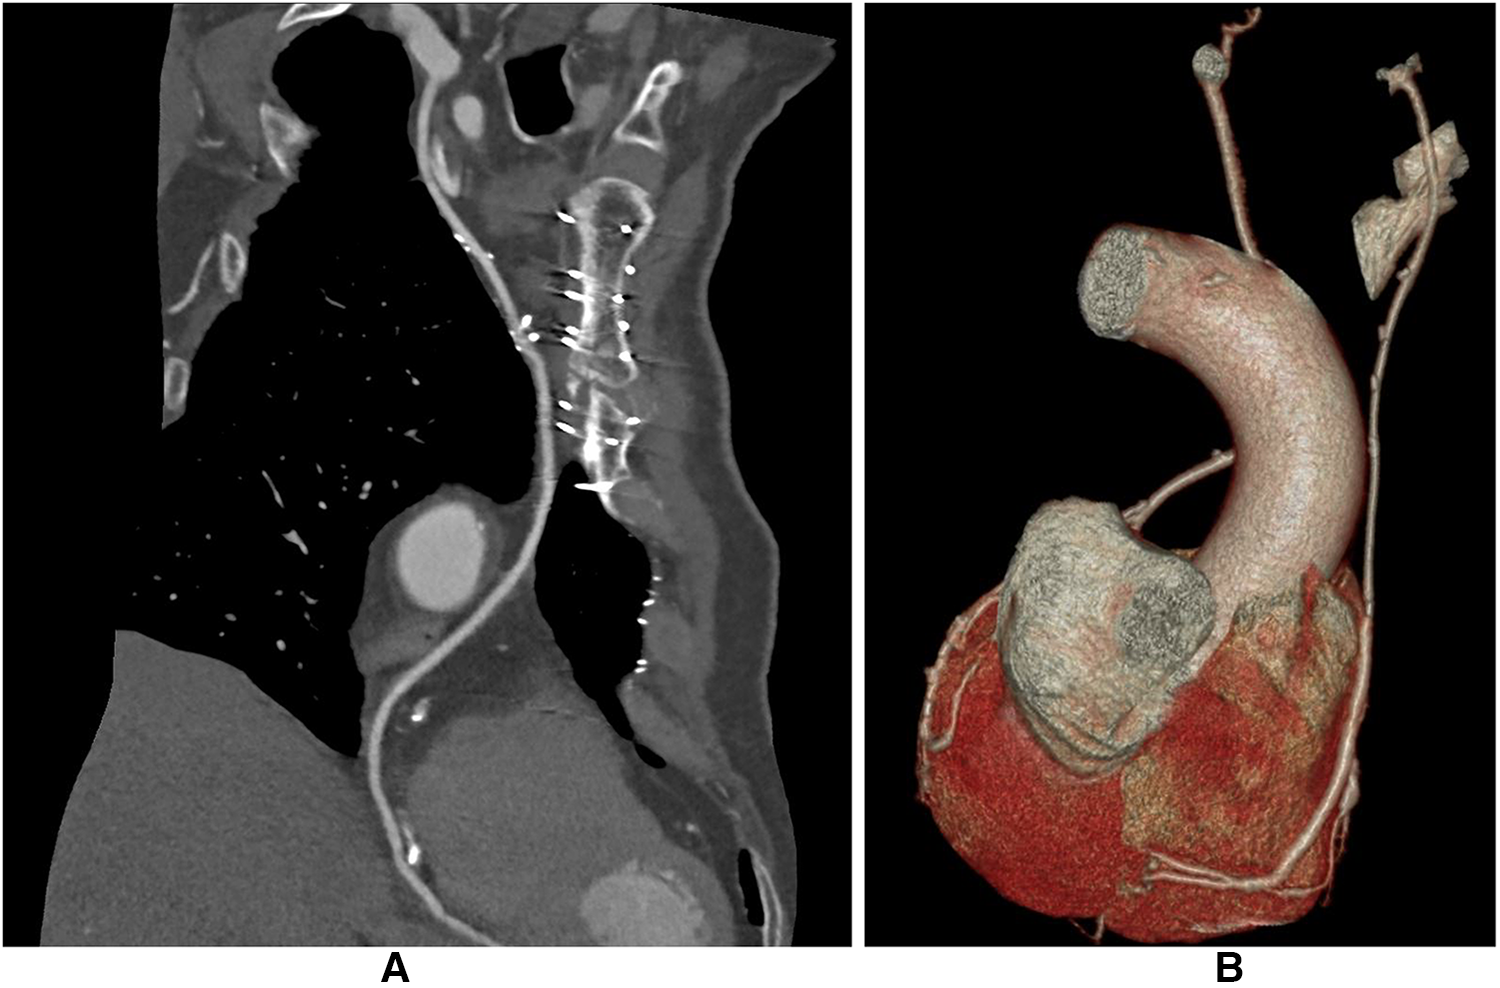

Postoperative CCTA was performed in 132 patients, 64 in the I-graft group and 68 in the Ao-group (Figure 3). Patients in the I-graft group had a mean follow-up time significantly longer, 9 (7–11) vs. 6 (4–9) years, p < 0.0001. The 10-year Kaplan–Meier estimate of SVG patency was 70.4% ± 5.2, higher in the I-graft group than in that in the Ao-graft group (82.8% ± 6.5 vs. 58.8% ± 7.4, p = 0.0026).

Figure 3

CCTA after I-graft RITA-SVG distally anastomosed to PDA. The diameter of the SVG has with time the trend to become equal to that of RITA. (A) After 123 months the size of the SVG is similar to that of RITA. (B) After 138 months the size of the SVG is still slightly larger than the RITA. CCTA, computed coronary tomographic angiography; RITA, right internal thoracic artery; SVG, saphenous vein graft; PDA, posterior descending artery.

The inner lumen diameter of the SVG measured in the CCTA was larger in the Ao-graft group than that in the I-graft group (3.4 ± 0.6 vs. 2.7 ± 0.4 mm, p < 0.0001). In contrast, the inner lumen diameter of the RITA in the I-graft group was 2.4 ± 0.3, similar to that of the LITA in the Ao-graft group, 2.5 ± 0.4 (p = 0.1180).

Although we did not actively measure the SS, it is clear that the SVG tends to adapt to RITA size and sometimes the two vessels are difficult to distinguish (Figure 3A), in a process similar to that described by Huang et al. (57, 58) and Lobo Philo et al. (59). This resulted not only in a higher 10-year patency compared to SVG from the aorta but also in a higher freedom from MACE, as the I-graft most likely behaves more like an arterial graft than a hybrid graft. These data are the result of a strategy that may improve the patency rate of SVG to RCAs.